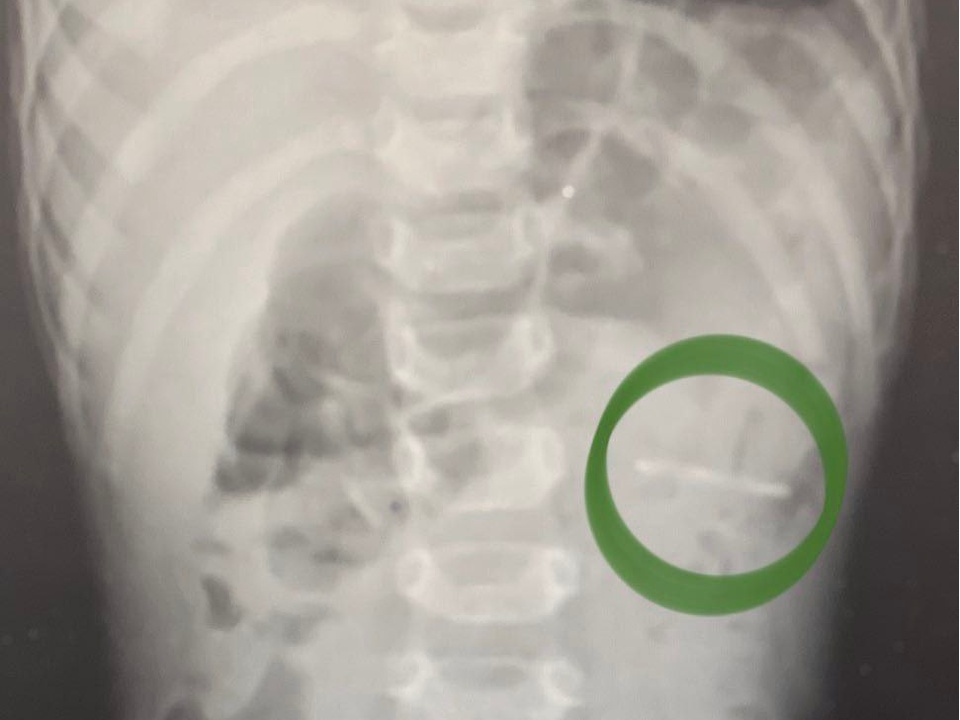

Годовалый ребенок нечаянно проглотил крупный ключ-открывашку от алюминиевой банки. Родители немедленно привезли мальчика в приемное отделение Раменской больницы. Ребенку выполнили рентген-исследование органов брюшной полости и смогли обнаружить расположение предмета — он был в желудке.